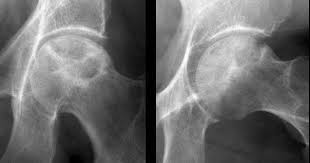

Veleszületett csípőficam csípőízületi dyspalsia

A csípőszűrés célja: a veleszületett csípőficam illetve un. csípőízületi dysplasia kiszűrése és időben történő kezelés megkezdése.

A csípőízületi fejlődési rendellenességek kiszűrésének jelentősége az, hogy az élet későbbi szakaszában kialakuló járási rendellenességeket megelőzzük. Felismerésre nem kerülő vagy nem kezelt illetve nem időben kezelt csípőízületi rendellenességek a későbbi életkorban végtagrövidüléssel, ízületi mozgásbeszűküléssel, ezekből következő sántító járással, gyors csípőízületi kopással, és állandó fájdalommal járnak.

A nem kezelt veleszületett csípő rendellenesség felgyorsítja a csípőízület kopását, ami általában 40 éves kor körül csípőízületi protézis beültetést tesz szükségessé.

Csípőízületi porckopás (coxarthrosis)

A csípőízületi porcfelszínek elkopása – az ún. artrózis – igen gyakori betegség. Enyhe formájában csak kifejezett terhelés során jelentkezik mérsékelt csípőtáji fájdalom, azonban a súlyos kopás a járást is erősen megnehezíti, vagy akár járásképtelenséget is okozhat, az életminőséget jelentősen rontva.

A csípőízület kopását elősegítő tényezők:

- a túlsúly

- a kifejezett mozgásszervi túlterhelés

- genetikai hajlam

- csípőízület fejlődési zavarai (csípőficam, diszplázia)

- egyes gyermek- és serdülőkori combfej betegségek (combfej elhalás, combfej elcsúszás)

- az autoimmun ízületi gyulladások (pl. a reumatoid artritisz)

- a combfej felnőttkori elhalása, beroppanása

A csípőízületi kopás kezdeti szakaszában jellemző a terhelésre jelentkező csípőtáji fájdalom, valamint a hosszabb pihenés utáni első lépések fájdalmassága, (un. indítási fájdalom) mely néhány lépés után “bejáródik”. Ilyenkor a csípőízületi porcfelszín felpuhulása, később annak felrostozódása figyelhető meg, mely a fokozatosan leváló kisebb rostok miatt az ízület izgalmi állapotát, gyulladását eredményezi; utóbbi felelős a fájdalom kialakulásáért.

A betegség korai szakaszában a cél az ízületi gyulladás csökkentése, a fájdalom megszüntetése, a kiváltó ok kezelése. A lehetőségek:

- pihentetés

- gyulladáscsökkentő gyógyszer, kenőcs

- gyulladáscsökkentő injekció

- tablettás, kapszulás vagy por kiszerelésű porckészítmény

- ízületi kenést biztosító és a porcfelszínt ellenállóbbá tevő ízületi injekció

Előrehaladott csípőízületi porckopás esetén a fenti lehetőségeken kívül műtéti megoldás jön szóba, csípőízületi protézis beültetés formájában.